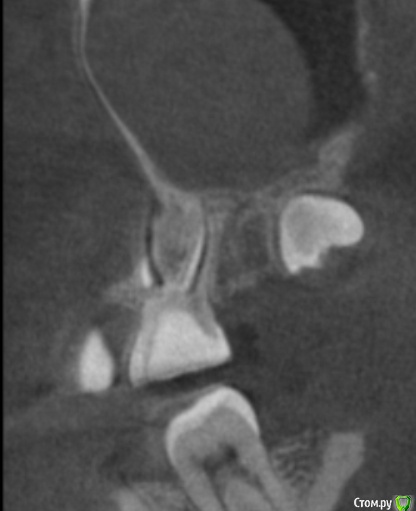

tineola Опубликовано 11 марта, 2017 Поделиться Опубликовано 11 марта, 2017 (изменено) Уважаемые врачи, здравствуйте! Мне 31 год, пол женский. Хронология:1. Ноябрь 2015 г. - септопластика и удаление кисты в левой гайморовой пазухе.2. Июль 2016 г. - со стороны этой же пазухи пролечены каналы 6-ки, через неск. дней удалена соседняя 7-ка (опустился почти до десны, беспокоил, ортодонты сошлись во мнении, что надо удалять).Через неделю появились незначительные боли в 6-ке, возникающие безотносительно нагрузки на зуб и еду. На прицельном рентгене корни 6-ки и лунка от 7го зуба были в порядке. Стоматолог уверял, что боль вызвана заживлением лунки от удаленного зуба и много других версий. Поэтому я ждала улучшений и терпела все это время.3. В последние недели боль усилилась: возникает при поворотах, наклонах головы, появились головные боли, головокружения, заложенность в носу. Сделала КТ конкретной области беспокоящего зуба, на которой видно новообразование в левой гайморовой пазухе, как бы лежащее на корнях беспокоящей 6-ки. Стоматологи предполагают, что киста от зуба мудрости (т.е. одонтогенная), возможно, рецидив первой. К посту прикрепила:1. ОПТГ (сделана до лечения 6-ки и удаления 7-ки, но после септопластики и удаления кисты).2. Фото из свежей КТ зубов с разных ракурсов, где хорошо видно новую кисту; ссылка на Яндекс-диск с архивом этого КТ (около 350 Мб) - https://yadi.sk/d/9omJkw6x3Efc6u3. Фото одной из проекций из старой КТ ОНП до септопластики, так выглядела старая киста. 4. К сожалению, результатов гистологии первой кисты у меня нет. В центре, где меня оперировали заключение не отдали, только сказали на словах, что все в результатах нормально. Попробую на руки получить...Очень интересует ваше мнение об увиденном на снимках.Правильно я понимаю: киста от зуба мудрости? удалять надо в ЧЛХ зуб с кистой вместе? Не пострадали ли от долгого ожидания решения проблемы корни 6-го зуба? Заранее большое спасибо за помощь! Изменено 11 марта, 2017 пользователем tineola Ссылка на комментарий

tineola Опубликовано 15 марта, 2017 Автор Поделиться Опубликовано 15 марта, 2017 (изменено) Сделала несколько скриншотов, прикрепляю к сообщению. Надеюсь, это то, что нужно.Может у кого-то из врачей будет время и возможность посмотреть КТ (ссылка в первом сообщении поста). Получила результаты гистологии первой кисты пазухи, которая год назад была удалена:Микроописание: Присланный материал представлен фрагментом полипозно-отечной слизистой оболочки, с концевым отделами слизисто-серозных желез. Эпителий слущен, гиалиоз базальных мембран, строма резко отечна, с диффузной лимфоцитарно-лейкоцитарной инфильтрацией. Патзаключение: хронический воспалительный процесс. Изменено 15 марта, 2017 пользователем tineola Ссылка на комментарий

tineola Опубликовано 15 марта, 2017 Автор Поделиться Опубликовано 15 марта, 2017 Еще скриншоты. Другая проекция из КТ. Ссылка на комментарий